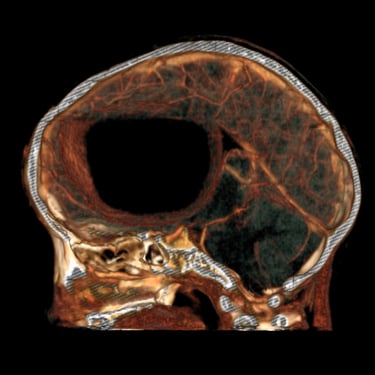

El absceso cerebral es una infección localizada del parénquima cerebral que produce acumulación de pus e inflamación, generando cefalea, fiebre, alteración del estado de conciencia o déficit neurológico focal. El diagnóstico temprano es fundamental para evitar complicaciones graves. La tomografía cerebral con contraste es el estudio de elección inicial, ya que permite visualizar una lesión hipodensa con realce en anillo característico. Posteriormente, la resonancia magnética complementa la evaluación. El tratamiento combina antibioticoterapia dirigida y, en casos seleccionados, drenaje quirúrgico o resección. La detección oportuna mediante imágenes mejora significativamente el pronóstico del paciente.